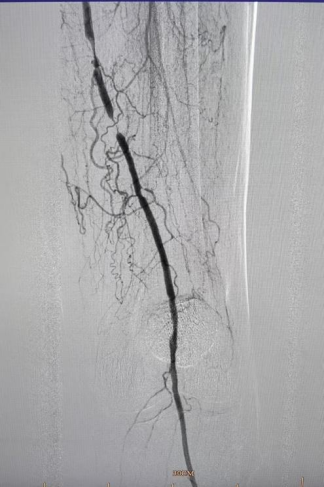

★ 造影评估

右侧股动脉翻山入路,经鞘管造影显示下肢动脉多发硬化改变。

左侧股浅动脉中下段局部重度钙化狭窄闭塞,左股浅动脉下段,腘动脉局部中度钙化狭窄。

★ 管腔准备

导管配合V-18 control wire通过病变段到达远端胫前动脉,交换V-14 control wire,引入Shockwave IVL M5(5.0×60mm)。冲击波球囊低压慢扩左侧腘动脉、股浅动脉下段钙化病变段(将球囊充盈至4atm后,激发震波,在完成一组脉冲后,将球囊缓慢充盈至6atm并持续60秒)